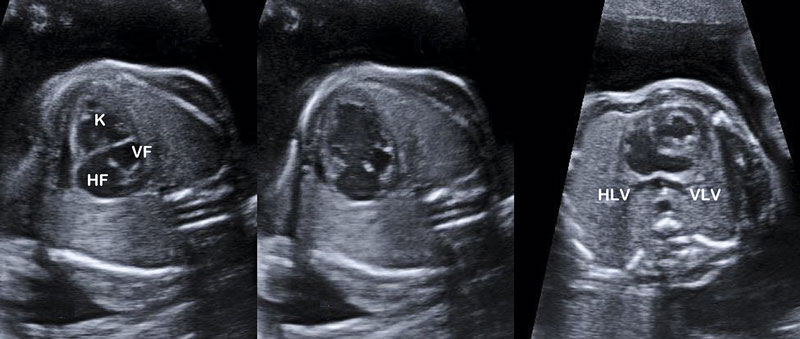

Tvillingtransfusionssyndromet. I Sverige görs därför fetoskopi i princip bara vid potentiellt letala tillstånd, framför allt vid tvillingtransfusionssyndrom. Kortfattat är syndromet en konsekvens av obalans i blodflödet i kommunicerande kärl mellan fostren – anastomoser i den gemensamma placentan – som alltid finns i en monokorionisk (monoplacentär, enäggstvilling-) graviditet Figur 1 [1].

Den kausala behandlingen är att stänga anastomoserna, och för detta används fetoskopi för att identifiera kärlen och därefter koagulera dem med laserenergi som fortleds via en tunn laserkabel i en arbetskanal i feto­skopet (Figur 2).

Figur 2